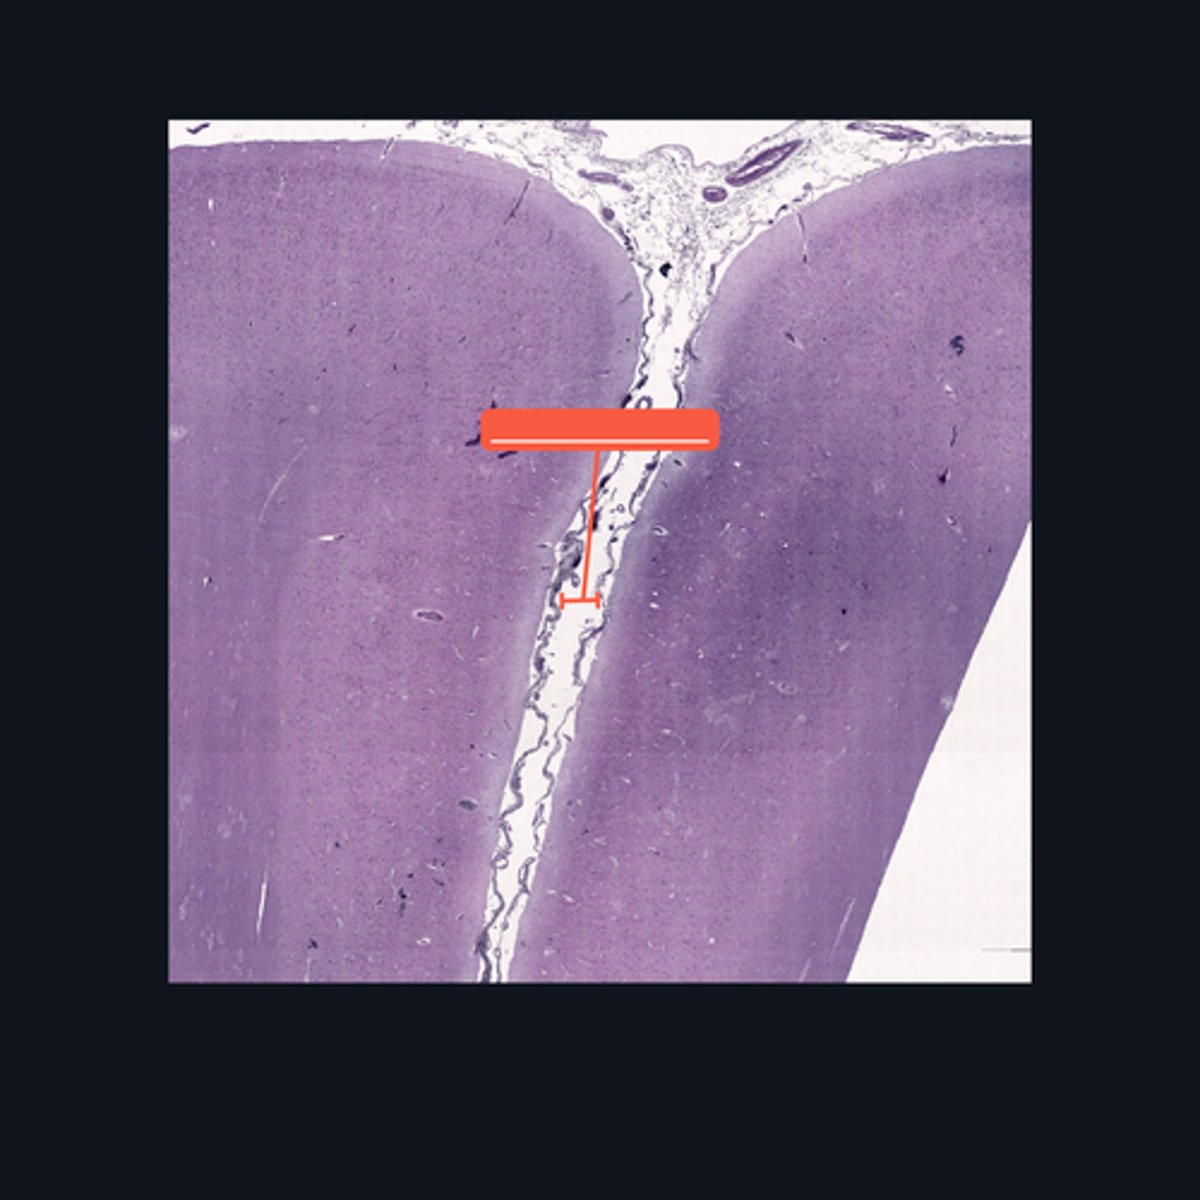

Identify the region of the spinal cord in the given image.

(top to bottom)

Ventral median fissure

White matter

Ventral horns

Central Canal

Central commissure

Dorsal midline sulcus

Dorsal horns

Identify the parts of the sacral region of the spinal cord.

FALSE

T or F: The white matter in this region of the spinal cord is larger than the white matter in the thoracic region of the spinal cord.

Upper Cervical region

Identify the region of the spinal cord in the given image.

(top to bottom)

White matter

Ventral horn of gray matter

Central canal

Central Commissure

Dorsal horn of the gray matter

Dorsal Midline Sulcus

Identify the structures found in the upper cervical region of the spinal cord.